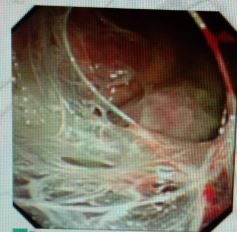

且看胸腔镜:

胸腔里面这么多分隔,你能保证你的针在哪个小分隔里面?除非你有孙悟空的火眼金睛!

在胸腔镜下,是“蜘蛛网+蜂窝状”般的变态存在。

你说说,这种情况怎么愉快的抽胸水?